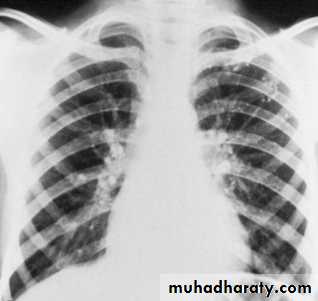

Neoplasm : Primary carcinoma of the bronchus frequently presents as a hilar mass.

If lobar collapse/consolidation or narrowing of the adjacent bronchus is visible the diagnosis of carcinoma is virtually certain.